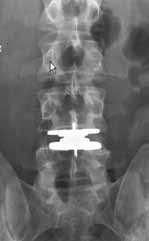

Fick min dom i veckan. Tre diskbuktningar som klämmer på tre olika nerver. L5-S1,L4 samt L3.